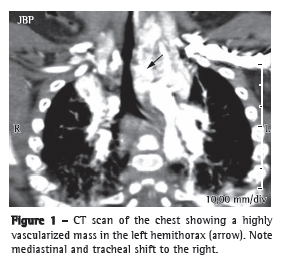

A CT scan of the chest, larynx, and trachea showed a heterogeneous, highly vascularized mass in the left hemithorax (Figure 1). However, there was no cardiac malformation. Rigid bronchoscopy performed under general anesthesia revealed a large pulsatile mass that obstructed approximately 80% of the larynx and trachea (Figure 2a; Video 1 ). On the basis of the radiological and endoscopic findings, a diagnosis of hemangioma was made. Because of the risk of bleeding, we decided not to perform a biopsy.